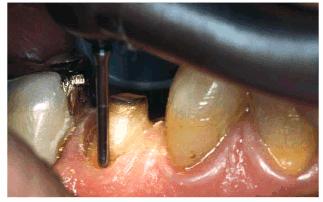

Figur 323s1823d e 18-3B: The initial preparations for the

three porcelain laminates were done with a 0.5-mm depth cutter (Brasseler LVS

System, Brasseler,

Figur 323s1823d e 18-3C: The two-grit diamond is used to reduce the enamel to the predetermined depth cut.

Figur 323s1823d e 18-3D: The final preparations.